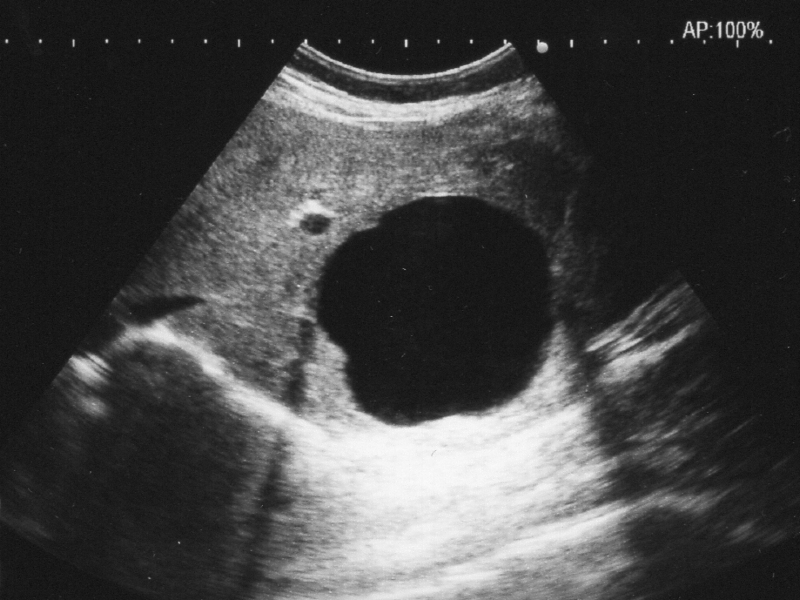

超音波の生体内特性により、ある条件下(音速の異なる境界に斜入射した場合)で超音波ビームが屈折する。超音波の屈折は、画像を歪ませたり、位置を左右方向へずらして表示したり、二重に表示されたりすることがある。また、超音波が屈折することによりビームが到達しない領域ができることもあり、その代表が腫瘤外側後方に出現する側方陰影である。

また、超音波ビームの屈折により後方の構造物が二重に表示されることがある。レンズ効果と呼ばれ、屈折が原因で観察されるアーチファクトである。